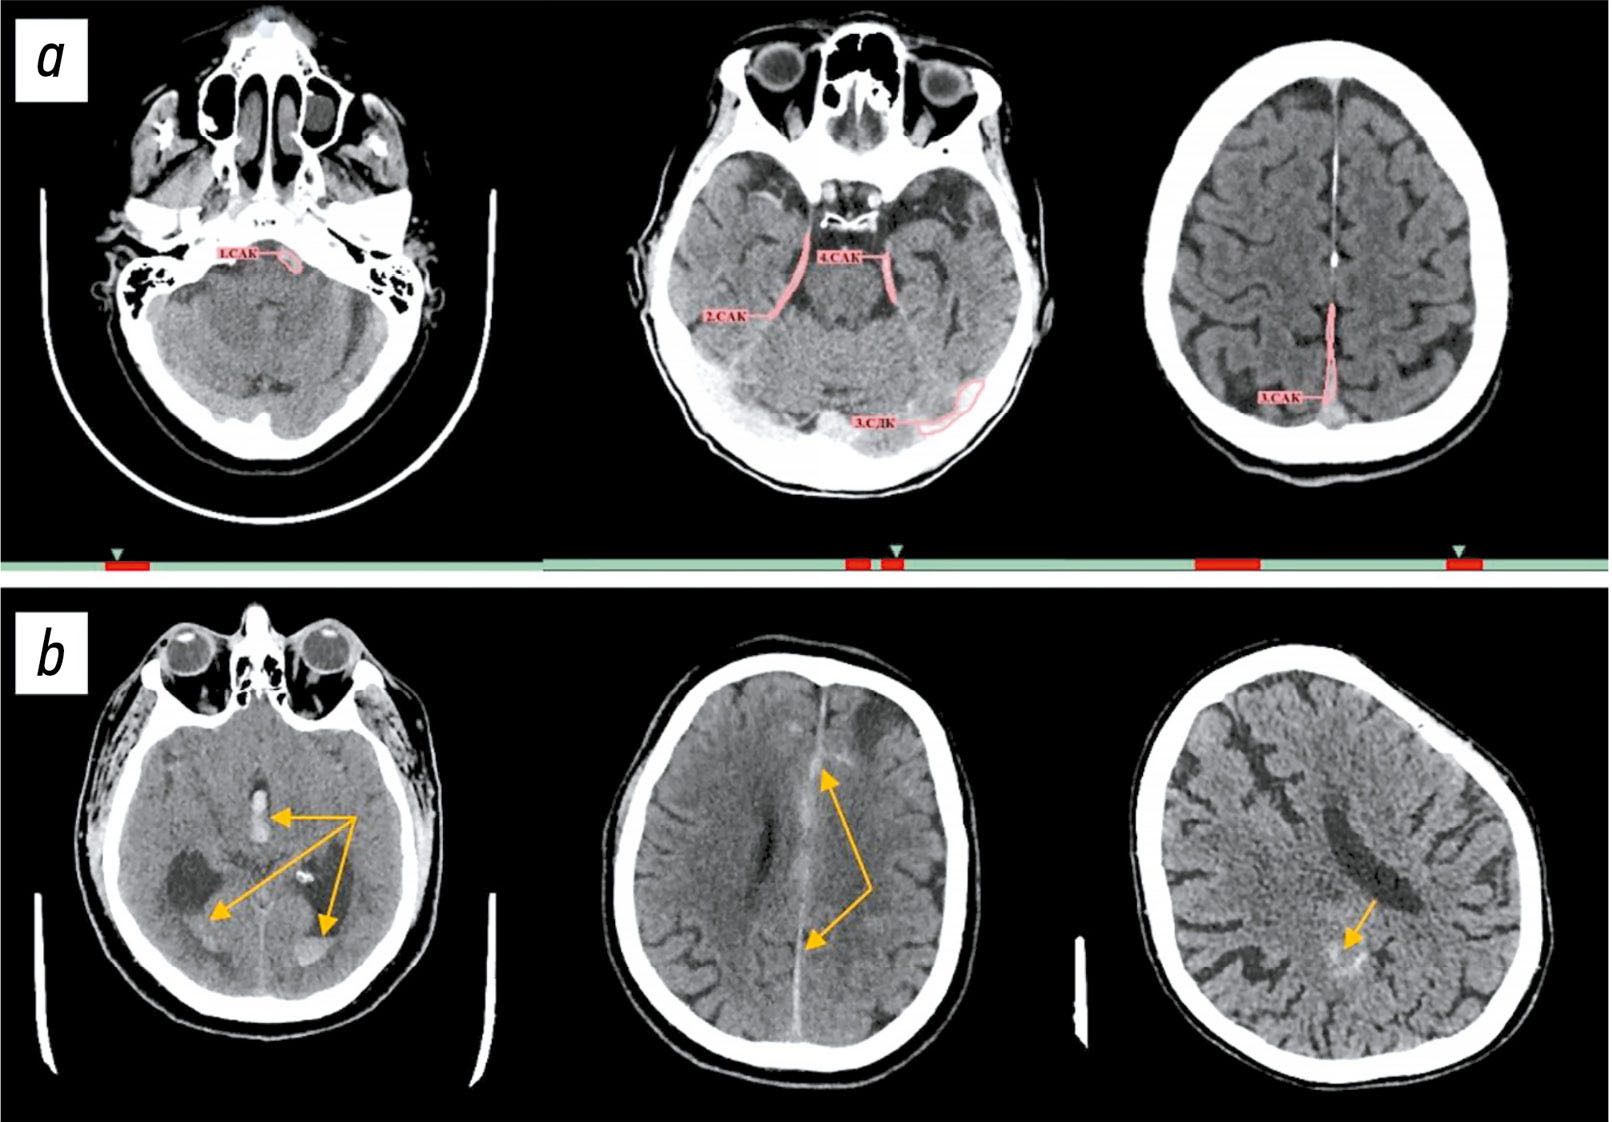

Одним из наиболее частых примеров частично корректного срабатывания можно назвать случаи, когда при множественных кровоизлияниях ИИ-сервис выделял один тип кровоизлияния, но пропускал другой. Так, на рис. 4, a слева пропущено внутримозговое кровоизлияние в левом полушарии, а на рис. 4, c слева ИИ-сервис корректно его сегментировал в левом полушарии, но не отметил внутрижелудочковое кровоизлияние в правом полушарии, а также межполушарное субарахноидальное кровоизлияние и по бороздам в обоих полушариях. Также частым случаем некорректных срабатываний является частичная сегментация кровоизлияния с ошибочным определением его типа (см. рис. 4, c) — справа представлено субдуральное кровоизлияние, которое ИИ-сервис идентифицировал как субарахноидальное. Гораздо реже среди примеров частично корректного срабатывания можно отметить полностью корректную сегментацию патологической зоны кровоизлияния, но неверное определение его/их типа (см. рис. 4, b) — справа внутримозговое кровоизлияние ошибочно классифицировано как субдуральное, а слева субдуральное кровоизлияние отнесено к субарахноидальному.

Рис. 4. Примеры частично корректных срабатываний сервиса искусственного интеллекта: a — корректное определение типа кровоизлияния и некорректная их сегментация; b — корректная сегментация областей кровоизлияния, ошибочное определение их типа; c — частичное выделение одних кровоизлияний и пропуск других, некорректные как сегментация, так и определение типа.

Всего отмечено 152 ложноположительных результата. Наиболее частыми их причинами являлись сегментации магистральных артерий, венозных синусов и частично кальцифицированных оболочек мозга (рис. 5, a).

Рис. 5. Примеры ложно-положительных (a) и ложноотрицательных (b) срабатываний сервиса искусственного интеллекта.

ИИ-сервис не выявил патологические изменения на 14 изображениях КТ ГМ. Наиболее часто встречали ложноотрицательные результаты при субарахноидальных кровоизлияниях — 8 случаев (см. рис. 5, b, в центре и справа). Реже наблюдали пропуски внутрижелудочковых кровоизлияний — 2 случая (см. рис. 5, b, слева), внутримозговых кровоизлияний — 2 случая, а также по одному случаю субдурального и эпидурального кровоизлияния.